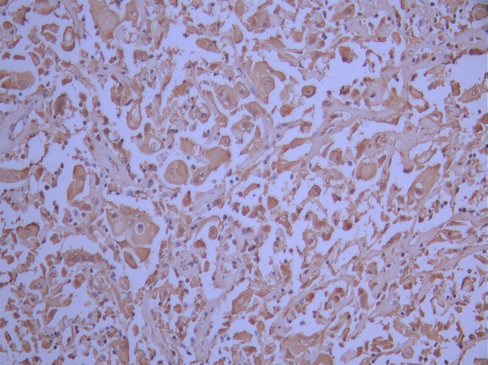

• IHC image of CSB-RA181279A0HU diluted at 1:100 and staining in paraffin-embedded human cervical cancer performed on a Leica BondTM system. After dewaxing and hydration, antigen retrieval was mediated by high pressure in a citrate buffer (pH 6.0). Section was blocked with 10% normal goat serum 30min at RT. Then primary antibody (1% BSA) was incubated at 4°C overnight. The primary is detected by a Goat anti-rabbit polymer IgG labeled by HRP and visualized using 0.05% DAB.